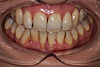

L'aménagement des tissus gingivaux dans le cadre des traitements implantaires

Un implant est envisagé pour remplacer une incisive perdue, mais le volume de gencive résiduelle est trop faible.

Une greffe de gencive concomitante à la pose de l'implant permet de retrouver un volume de gencive adéquat.